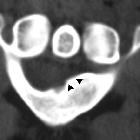

Musculus brachialis accessorius